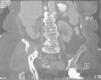

Masa glútea en anciana con enfermedad de Paget del hueso

A. Ballarín González, P. Laguna del Estal, H. de la Torre Martí, J.M. Palau Fayos

Servicio de Medicina Interna. Hospital Universitario Puerta de Hierro. Madrid. España